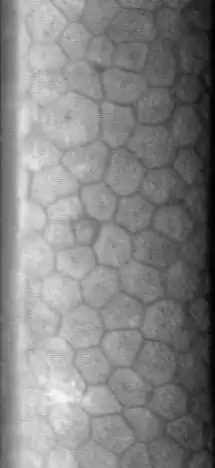

Hexagonal cells of corneal endothelium visualized by specular microscopy.

The normal corneal endothelium is a single layer of uniformly sized cells with a predominantly hexagonal shape. This honeycomb tiling scheme yields the greatest efficiency, in terms of total perimeter, of packing the posterior corneal surface with cells of a given area. The corneal endothelium is attached to the rest of the cornea through Descemet's membrane, which is an acellular layer composed mostly of collagen IV.